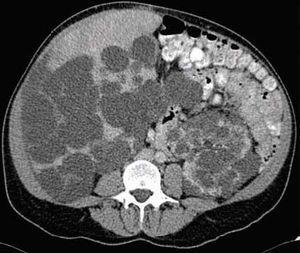

Paciente de 48 años con dolor abdominal en epigastrio, aumento del perímetro abdominal, saciedad temprana, plenitud posprandial y disnea de medianos esfuerzos. El examen físico: T/A: 140/100 IMC: 24.3kg/m², área hepática de 22 cm y hepatodinia. Química sanguínea: Creatinina: 1.06 mg/dL, ALT: 65 UI/L, AST: 28 UI/L, bilirrubina total: 0.67 mg/dL; directa: 0.07 mg/dL. Fosfatasa Alcalina: 60 UI/L.

Ultrasonido y tomografía con evidencia de enfermedad poliquistica del adulto. Se realizó fenestración laparoscopica de los quistes hepáticos, con adecuada evolución.

Figura 4. Enfermedad poliquística renal y hepática.